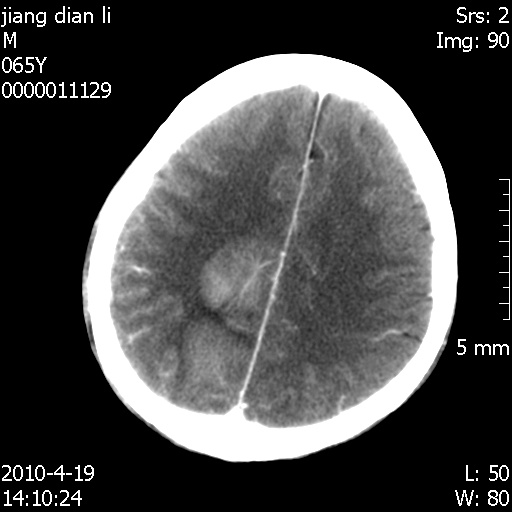

今天上班后发现病人前天复查(4月18日发病,19日初诊,22日复查),三个病灶均明显增大,边缘仍旧清楚,水肿加重,右侧脑室基本闭塞。

今天遇到临床医生,询问病人情况,病人已经死亡。

最后看到的病人右侧瞳孔呈针尖大小,估计是继发脑干梗死,而非脑疝死亡。

遗憾! 复习了复查片:发现顶叶出血灶破入侧脑室,侧脑室体部见少许高密度。